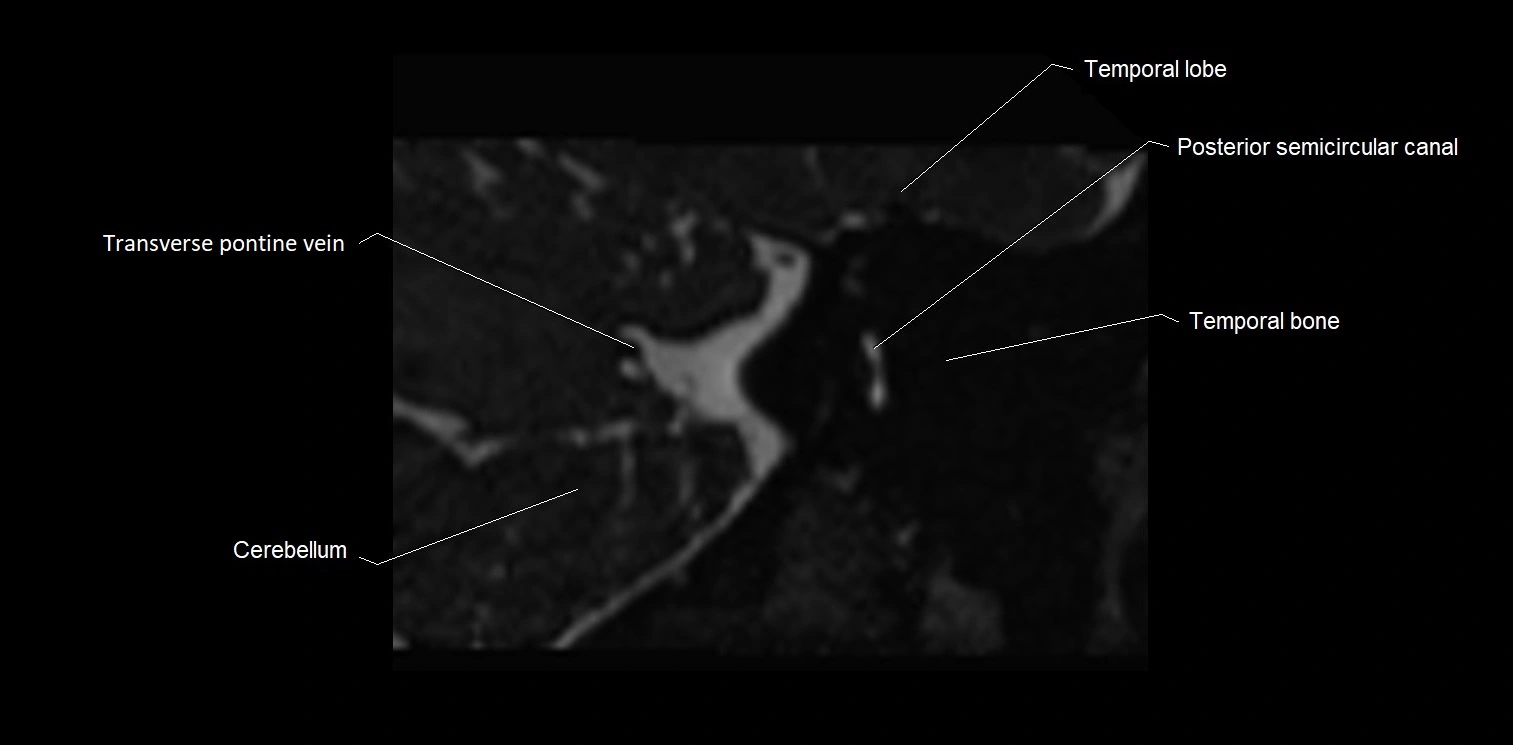

MRI images

image